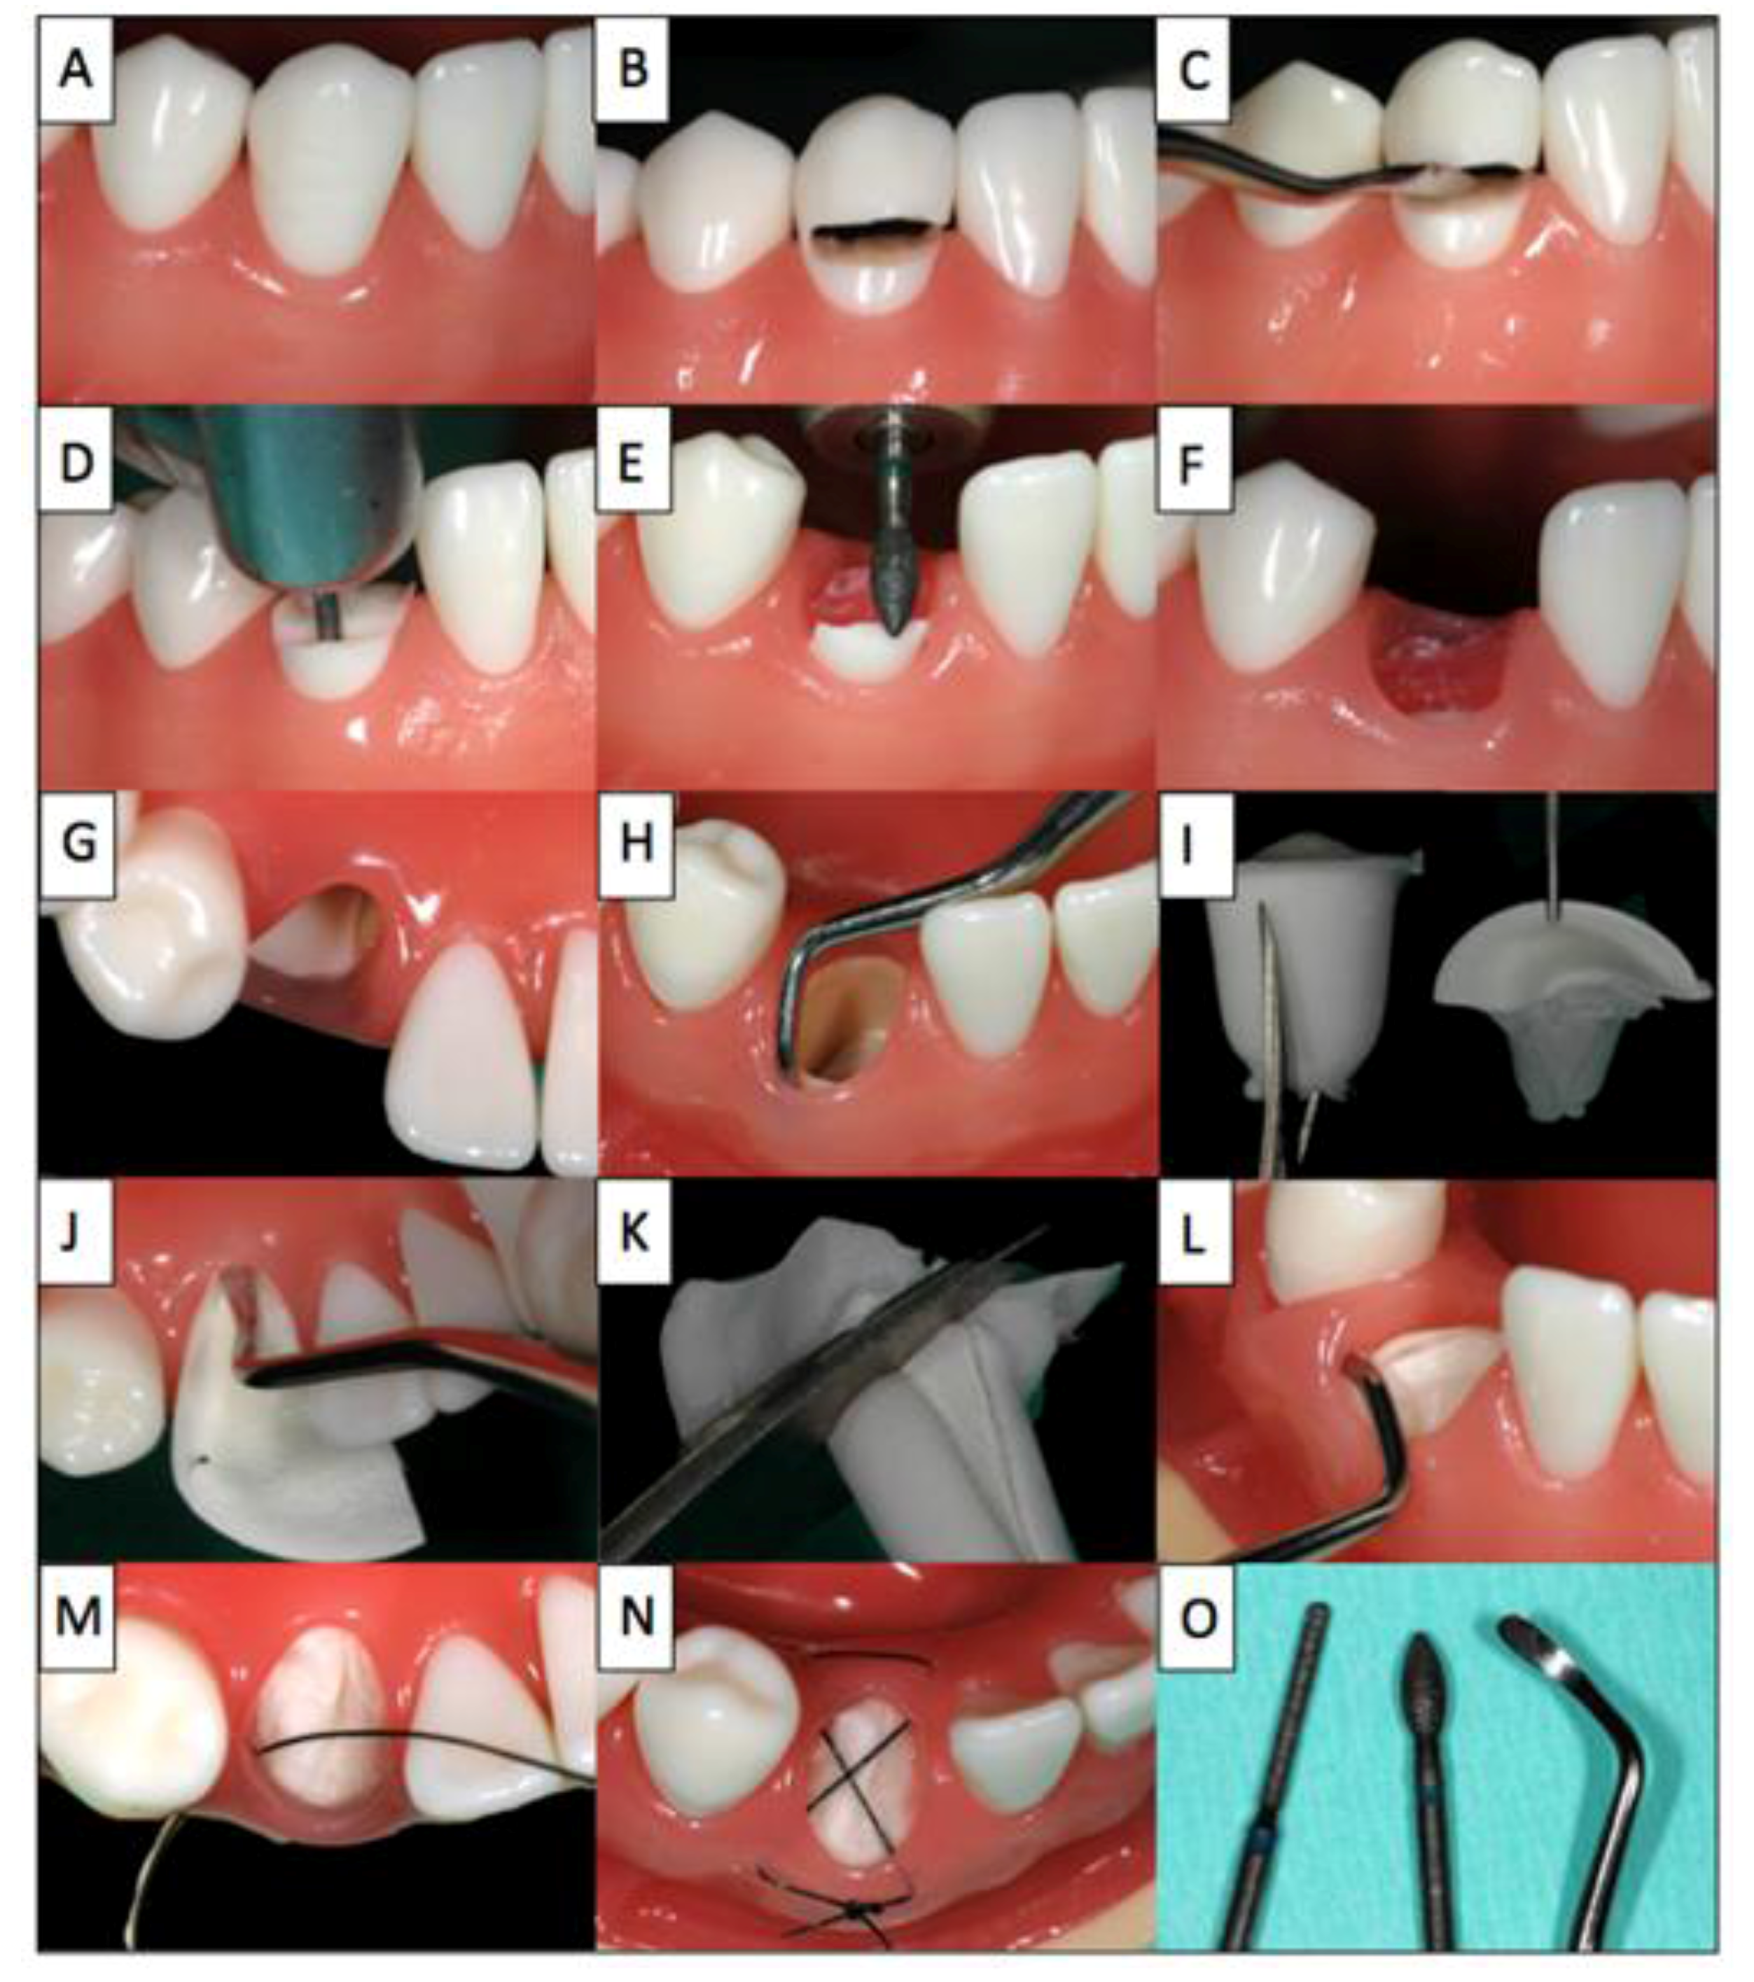

Treatment plan: Partial extraction of tooth 22 (A), prevention of the alveolar ridge resorption using the socket shield technique (B,C,D), late implantation (G) of a titanium implant (Nobel Biocare Replace®). The treatment is depicted in Figure 4.

Figure 4. Case 3.

Dentistry 02 00011 g004

De-epithelialisation of the wound margins with a diamond polisher (A); status post extraction with retention of the shortened and reduced root fragment (B); Absorbable cone inserted into the extraction socket secured with criss-cross suture (C); healing course following suture removal after 10 days (D); buccal view of the healing course after 30 days (E); occlusal view of the healing course after 30 days with intact buccal soft tissue contour (F); completely preserved buccal bundle bone with re-entry (G); optimum, slightly palatial shift of the implant (H); preoperative X-ray control, with socket shield in the healing phase, with inserted implant, with screwed crown (I).